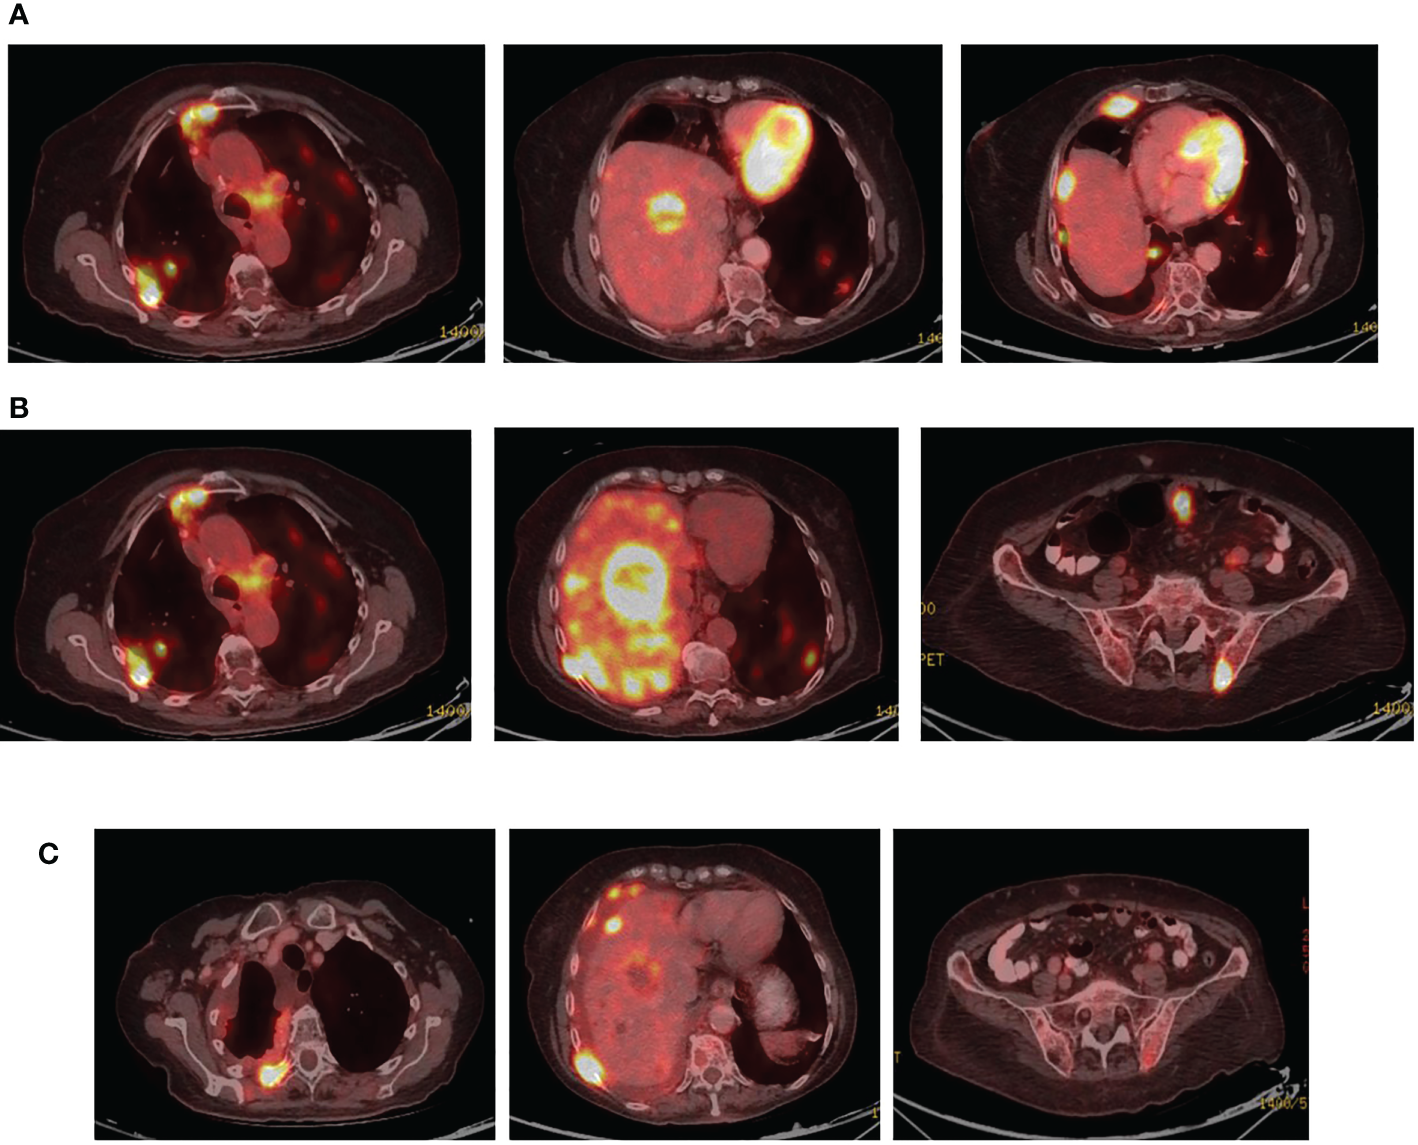

Disease progression in the right pleura was identified in November 2019 with a right-sided pleural effusion. Osimertinib was initiated, demonstrating a partial response (Figures 5A, B).

Figure 5

(A) Coronal PET-CT scan from November 2019 shows a pleural effusion and lesions with increased uptake of FDG-18, indicating disease progression. (B) Three months later, following Osimertinib demonstrated partial response. (C) February 2021, showing a new pleural lesion indicating disease progression on Osimertinib.

Upon mild local disease progression In February 2021, a lung biopsy, and a comprehensive genomic test (Tempus) were performed. Tissue biopsy demonstrated a poorly differentiated cancerous lesion with 50% Ki67 (neuroendocrine marker). At the same time a liquid biopsy resulted: EGFR exon 19 deletion (41%), EGFR T790M (11.9%), and a MKRN1-BRAF fusion gene, as shown in Table 2. In follow-up, the patient’s disease progression was mostly stable containing small nodules in the lungs (Figure 5C).

Osimertinib alone was continued until June 2021, at which time there was further disease progression into the pleura, liver, peritoneum, and bones (Figure 6A). To combat this, the patient underwent 3 cycles of carboplatin and pemetrexed, alongside Osimertinib with further disease progression (Figure 6B).

Figure 6

(A) Coronal PET-CT scan, from June 2021, showing new multiple lung and liver lesions with increased uptake of FDG-18, indicating further disease progression on osimertinib. (B) Two months later, August 2021, they demonstrated massive disease progression with lung, liver, and bone metastases following chemotherapy plus Osimertinib. (C) Three months later, November 2021, showed significantly decreased uptake of FDG-18, indicating partial response following adding dabrafenib plus trametinib to Osimertinib.

In August 2021, osimertinib was initiated alongside BRAF kinase inhibitor trametinib and dabrafenib, to combat the MKRN1-BRAF fusion gene acting as a mechanism of resistance. This resulted in clinical and RECIST partial response (Figure 6C). In February 2022, the patient passed away due to lung disease progression.